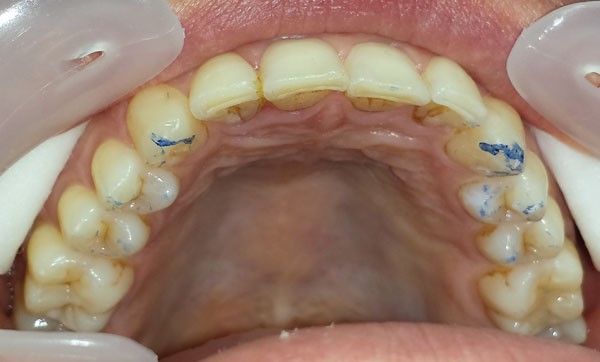

Le bruxisme est un sujet d’intérêt pour les chirurgiens-dentistes dont les patients présentent très fréquemment des lésions d’usure « inquiétantes ». Si les données récentes permettent de mieux en appréhender les mécanismes physiopathologiques et les possibilités thérapeutiques, la cohabitation durant des décennies de théories totalement différentes a pu rendre le sujet peu clair pour l’omnipraticien. Ainsi, les méthodes diagnostiques et de prise en charge semblent très différentes d’un praticien à l’autre. L’objectif de l’évaluation des pratiques professionnelles (EPP) des praticiens était de mesurer ces divergences. Cet article présente les résultats de l’EPP, et propose en réponse au questionnaire quelques éléments actuels de connaissances et de pratique clinique sur le sujet.

94 % des praticiens ont répondu définir le bruxisme par un grincement et 79 % par un serrement des dents. Seulement 14 % le définissent par tapotement des dents et 4 % par une hyperactivité mandibulaire sans contacts occlusaux. 8 % des participants ont répondu que le bruxisme se manifestait uniquement la nuit (fig. 1).